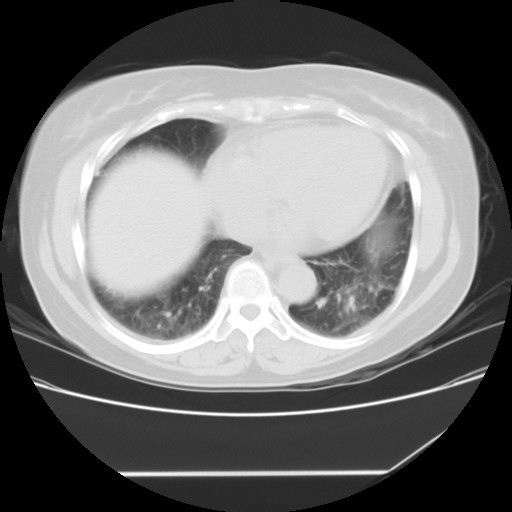

女性,62岁,长期咳嗽,既往从事工作有粉尘接触,有高血压病史,110/150mmhg,近日咳嗽加重,脸面浮肿,请大家帮看下,

1、尘肺;2、慢性支气管炎合并肺部感染;3、心影增大(左房、左室大),考虑高血压性心脏病。

慢支并肺部炎症;右肺结核球?主肺动脉、右肺动脉影不宽,右心室不大,不支持肺心病;无心包积液。

间质性肺炎,有纤维化趋势。

1)慢性支气管炎并肺部感染、肺气肿。2)肺间质纤维化。

间质性肺炎,左下肺机化性肺炎。